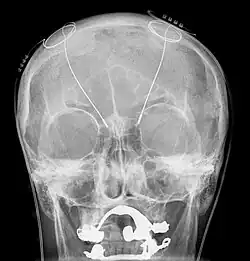

Estimulação cerebral profunda ou ECP (do inglês Deep Brain Stimulation (DBS)) é um tratamento neurocirúrgico para transtornos neurológicos usando um marcapasso cerebral que envia impulsos elétricos a determinada parte do encéfalo. É usado no tratamento de doenças neurológicas em que a medicação não foi eficiente e que causa amplos prejuízos ao paciente.[1]

Com a instalação cirúrgica de eletrodos no cérebro, um controle externo permite regular a estimulação elétrica da áreas subcorticais com déficit neurológico e assim reequilibrar os circuitos neuronais danificados diminuindo a frequência de problemas como tremores, rigidez e contrações musculares involuntárias. Mesmo sem medicação complementar diminui aproximadamente 57% desses sintomas.[12]

Recentemente um grupo de pesquisadores brasileiros liderado pelo neurocirurgião Erich Fonoff descreveu uma nova técnica de implante simultâneo de eletrodos para estimulação cerebral profunda bilateral (ECP Bilateral Simultanea) fazendo possível que o procedimento se tornasse mais rápido e preciso.[13][14] A precisão do implante faz toda a diferença pois a ECP tem seu efeito extremamente localizado.[15]